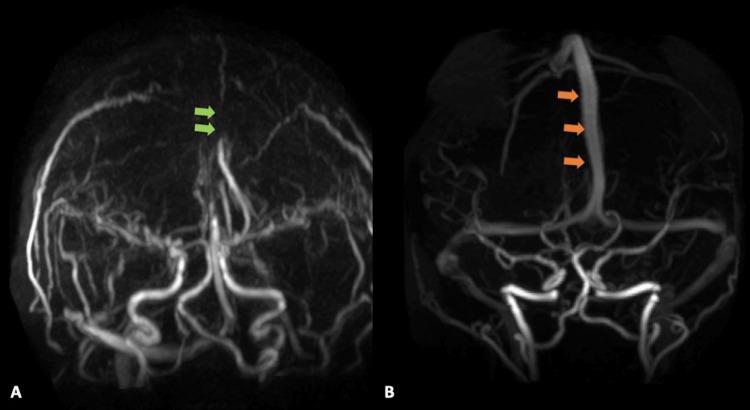

Ultra-low-dose combination estrogen-progestin contraceptive pills (OCP) have been marketed as being safer to use than previously higher estrogen-containing OCPs. While multiple large studies have shown a dose-dependent association between estrogen and deep vein thrombosis, there remains sparse guidance or data as to whether patients with sickle cell trait should avoid estrogen-containing OCPs regardless of the dosage. We present a case of a 22-year-old female with a history of sickle cell trait who had recently been started on an ultra-low-dose norethindrone-ethinyl estradiol-iron (1-20 mcg) that presented with headache, nausea, vomiting, and obtunded. Initial neuroimaging was significant for an extensive superior sagittal sinus thrombosis with extension into the confluence of dural venous sinuses, right transverse sinus, right sigmoid sinus, and right internal jugular vein which ultimately required systemic anti-coagulation. Her symptoms largely resolved within four days after starting anti-coagulation. She was discharged on day six to complete a six-month course of oral anti-coagulation. At her neurology follow-up three months later, the patient reported resolution of all symptoms. This study evaluates the safety of ultra-low-dose estrogen-containing contraceptive pills in the sickle cell trait population with special focus on cerebral sinus thrombosis.

超低剂量复方雌激素 - 孕激素避孕药(口服避孕药)已上市销售,宣传称其使用起来比以前含雌激素量更高的口服避孕药更安全。虽然多项大型研究表明雌激素与深静脉血栓形成之间存在剂量依赖性关联,但对于携带镰状细胞性状的患者是否应避免使用含雌激素的口服避孕药(无论剂量如何),仍然缺乏相关指导或数据。我们报告一例22岁有镰状细胞性状病史的女性病例,她最近开始服用超低剂量的炔诺酮 - 炔雌醇 - 铁(1 - 20微克),出现头痛、恶心、呕吐和意识模糊症状。最初的神经影像学检查显示广泛的上矢状窦血栓形成,并延伸至硬脑膜静脉窦汇合处、右侧横窦、右侧乙状窦和右侧颈内静脉,最终需要进行全身抗凝治疗。在开始抗凝治疗后的四天内,她的症状基本缓解。她在第六天出院,完成为期六个月的口服抗凝疗程。在三个月后的神经科随访中,患者报告所有症状均已消失。本研究评估了超低剂量含雌激素避孕药在镰状细胞性状人群中的安全性,特别关注脑窦血栓形成。